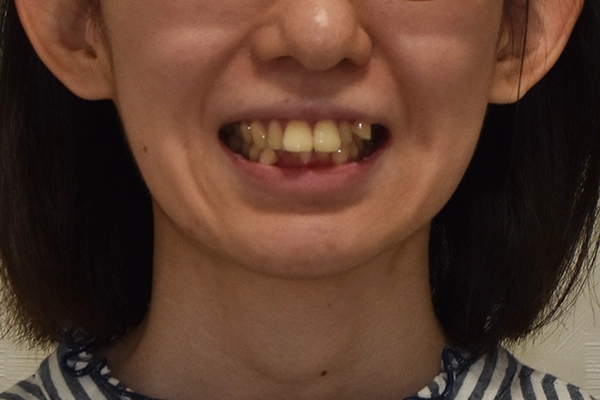

case.1 前歯のガタガタが

気になる

before

| 主訴 | 前歯のガタガタが 気になる |

|---|---|

| 治療期間 | 28ケ月 |

| 治療回数 | 30回 |

| 治療費 | 75万+税 |

| 治療内容 | クワドヘリックス バイヘリックス 上顎両側4番 7番抜歯 表側全体矯正 |

| リスク | 歯根吸収、歯肉退縮、 知覚過敏、歯の切削 |